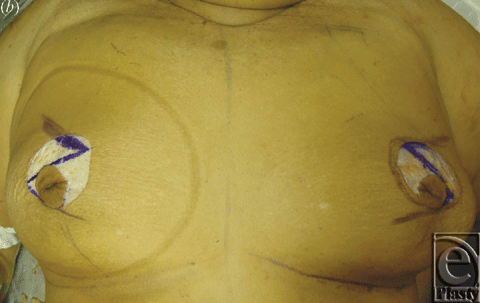

The breasts were approached either using a short vertical skin incision as described by Lejour and Abboud6 or via a periareolar skin incision. Surgical steps included skin incision, deepithelialization, and intraoperative marking of the planned glandular Z-plasty. The angles were chosen depending on breast size, shape, and degree of ptosis. The gland was then incised according to the form of the Z; flaps were undermined and transposed; and the inferior flap carried the nipple superiorly. For left-sided breasts, the Z was a mirror image of the right. For the short vertical skin incision group, the flaps were fully transposed. For the periareolar skin incision group, the flaps were partially transposed such that the superior flap was inset under the inferior Nipple bearing flap; this provided auto-augmentation. After glandular transposition of varying degrees and inset, the skin incision was then closed in the usual fashion. Photographs were taken to compare the breast appearance before and after the procedure (Figs 1 and 2), and the overall aesthetic appearance was graded on a scale from 1 (worst) to 5 (best).

Fifteen human cadaver dissections of the female breast were performed (2 formalin-preserved and 13 fresh) using 2.5x loupe magnification. The surgical concept for the Z-mammaplasty is to combine current successful and commonly used skin patterns with our new technique for glandular reorientation and lift. We performed the glandular Z-plasty using both vertical and periareolar skin incisions using fresh cadavers. Both skin patterns were followed by a Z-plasty in the breast gland and fat. The nipple was necessarily included on the inferior flap (by definition making it a superomedial pedicle). It is necessary to maintain the nipple on the inferior flap, to allow Z-plasty to achieve the primary goal of mastopexy, to raise nipple position. Following the dissection of breast tissue, the flaps of the z-plasty are transposed, causing the inferior segment containing the nipple to be lifted and buttressed by the transposed superior flap, which now lies at the inferior base of the breast. The following variables were measured both before and after glandular Z-plasty and compared by student t test: breast width, length, height, sternal-to-nipple distance, fold-to-nipple distance, midline-to-nipple distance, degree of ptosis (0nipple above inframammary fold, 1nipple at fold, 2nipple below fold but above lowest pole, and 3nipple at the lowest pole of the breast), areolar diameter, sternal notch-to-point A, length of vertical incision, distance above the fold where incision terminates, and length of circular incision for periareolar approach.

The inferior limb transposition moved the nipple superiorly and medially closer to the sternal notch and sternum midline an average of 5.3 ± 2.2 cm and 2.4 ± 1.7 cm, respectively. The average Z-plasty degree was 34.5 ± 8.2°. The average central limb length 8.7 ± 2.1 and average pedicle width was 5.4 ± 0.8 cm. An average of 1.8 perforators greater than 1 mm in diameter were visualized and divided to freely mobilize the inferior limb of the Z (ie, superior-medial pedicle with nipple). Buttress support of the nipple was accomplished by the caudal transposition of the superior Z-plasty flap and its inset below the nipple. A Benelli block technique was used to create a purse-string suture in the periareolar group before final skin closure. Finally, the average overall aesthetic result was 3.3 ± 0.9; the average vertical scar aesthetic result was 3.0 ± 0.8; and the average periareolar aesthetic result was 3.6 ± 1.0 (P = .2). Table 2 summarizes the aforementioned findings.